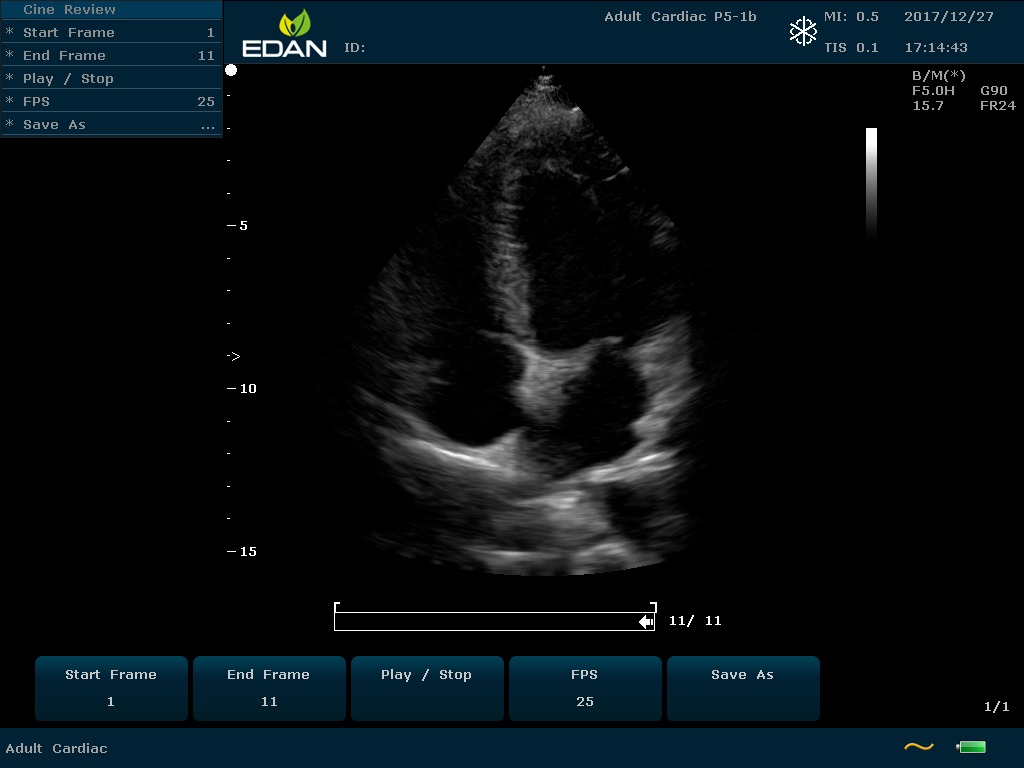

Особенность U60 Edan — расширенное применение. Ультразвуковой аппарат рекомендован для абдоминальных исследований, гинекологии и акушерства, кардиологии, педиатрии, урологии, изучения малых органов, сосудов. Для U60 Edan используются конвексные, линейные, фазированные и внутриполостные датчики.

Передовые технологии позволяют повысить качество визуализации в несколько раз. УЗИ-аппарат U60 Edan отличается возможностью быстрой настройки визуализации. Специальные функции позволяют моментально отображать данные за счет быстрой оптимизации параметров. Режимы визуализации: B-mode, M-mode, Color Doppler, Power Doppler Imaging, Pulsed Wave Doppler, Continuous Doppler.